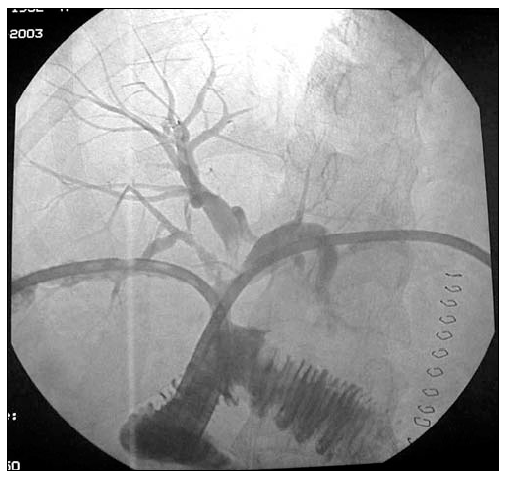

Figure 2. An iatrogenic pseudo-aneurysm of the right branch of the hepatic artery.

Finally, 7 porto-enterostomy anastomoses were performed (Figure 1e). In four cases, intraoperatively, the two major biliary systems were stented according to the Rodney-Smith technique with a transhepatic multi-fenestrated 8 french semi-rigid stent. The porto-enterostomy was indicated in six cases of complex iatrogenic biliary tract injury following laparoscopic cholecystectomy including one case associated with a major vascular injury (Figure 2). The final patient undergoing this anastomosis was a liver transplant recipient who developed a hepatic artery thrombosis leading to biliary duct stenosis. In 5 out of 7 cases the parashoot technique was employed for the anastomosis, while interrupted sutures were utilized in the remaining two cases.